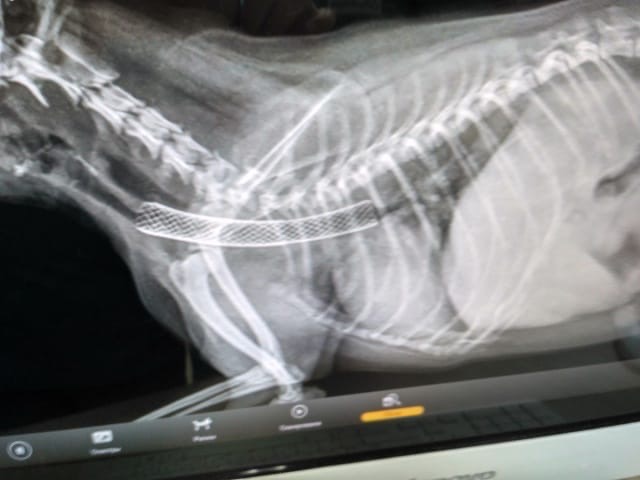

Точная диагностика и инновационное лечение мочекаменной болезни

Цистоскопия + дробление камней (литотрипсия): почему мы совмещаем диагностику и лечение за один визит

Стандартный сценарий при обнаружении камней в мочевом пузыре кошки — это диагноз «по УЗИ», затем тяжелая полостная операция (цистотомия) с разрезами, швами и долгим восстановлением. А если камень не один? А если это не камень, а опухоль? Мы уходим от этой лотереи

Это процедура введения тончайшего гибкого эндоскопа с HD-камерой в мочевой пузырь через уретру

Что она дает врачу (и вам):

Это золотой стандарт диагностики, после которого все сомнения исчезают

- Точный диагноз. Не «камень похож на оксалат», а «это струвитный камень размером 4 мм с рыхлой структурой». Или «это не камень, а полип».

- Оценку состояния слизистой. Врач видит степень воспаления, кровотечения, предраковые изменения.

- Возможность биопсии. При необходимости можно сразу взять образец ткани для анализа.

Лазерная литотрипсия

Как только диагноз «камень, требующий удаления» подтвержден, врач не достаёт эндоскоп. Он меняет насадку и проводит через рабочий канал того же прибора датчик литотриптора.

- Как это работает: Под прямым визуальным контролем зонд прибора точечно воздействует на камень, дробя его до состояния мелкого песка («пыли»), который затем вымывается или выводится естественным путем.

- Ключевое преимущество: Лечение мочекаменной болезни проводится сразу, в ходе той же самой процедуры, под той же анестезией. Не нужно дважды готовить животное к наркозу, дважды везти в клинику.